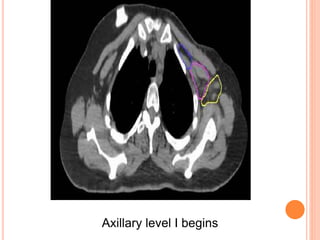

REGIONAL NODAL CONTOURING

Axillary level I begins